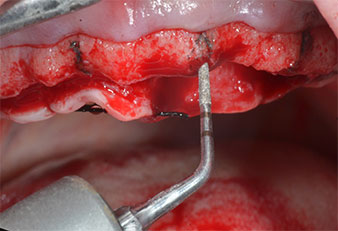

Uno strumento piezoelettrico (Piezomed I1) a forma di fiamma, rivestito in diamante, è stato usato per contrassegnare le posizioni dell'impianto e per eseguire una preparazione pilota (Fig. 3). Si è prestato attenzione a utilizzare un movimento verticale ascendente e discendente, con potenza ridotta, irrigazione completa e bassa pressione (inferiore a 300 g). Successivamente è stato applicato uno strumento pilota (Piezomed I2A/I2P) per l'ingrandimento iniziale delle sedi dell'impianto del diametro di 2 mm (Fig. 4), seguito da un inserto da 3 mm (Fig. 5).

Nel presente caso, gli strumenti Z25P e Z35P non sono stati utilizzati a causa dell'osso posteriore relativamente morbido, che è stato facilmente gestito mediante I3A/I3P.